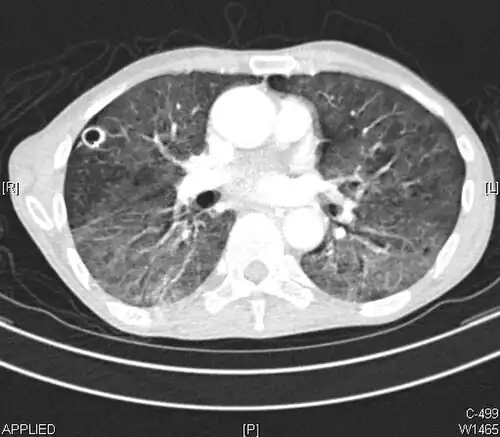

High-resolution CT image showing ground-glass opacities in the periphery of both lungs in a patient with COVID-19 (red arrows). The adjacent normal lung tissue with lower attenuation appears as darker areas.